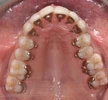

Dt. Elif Gündüz Diş Hekimi

Uzmanlık alanları

Diş hekim